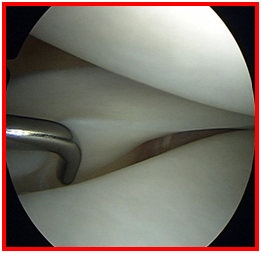

损伤的半月板

半月板损伤怎么样来修复呢,手术怎么做呢?

手术是通过关节镜来进行的,是非常微创的手术。一般两个小于1cm的切口就可以解决了。大部分患者仅适用两个小于1cm的切口,而且位于膝眼位置,

不仔细看看不出来。利用关节镜技术把损伤的半月板修整缝合加固。